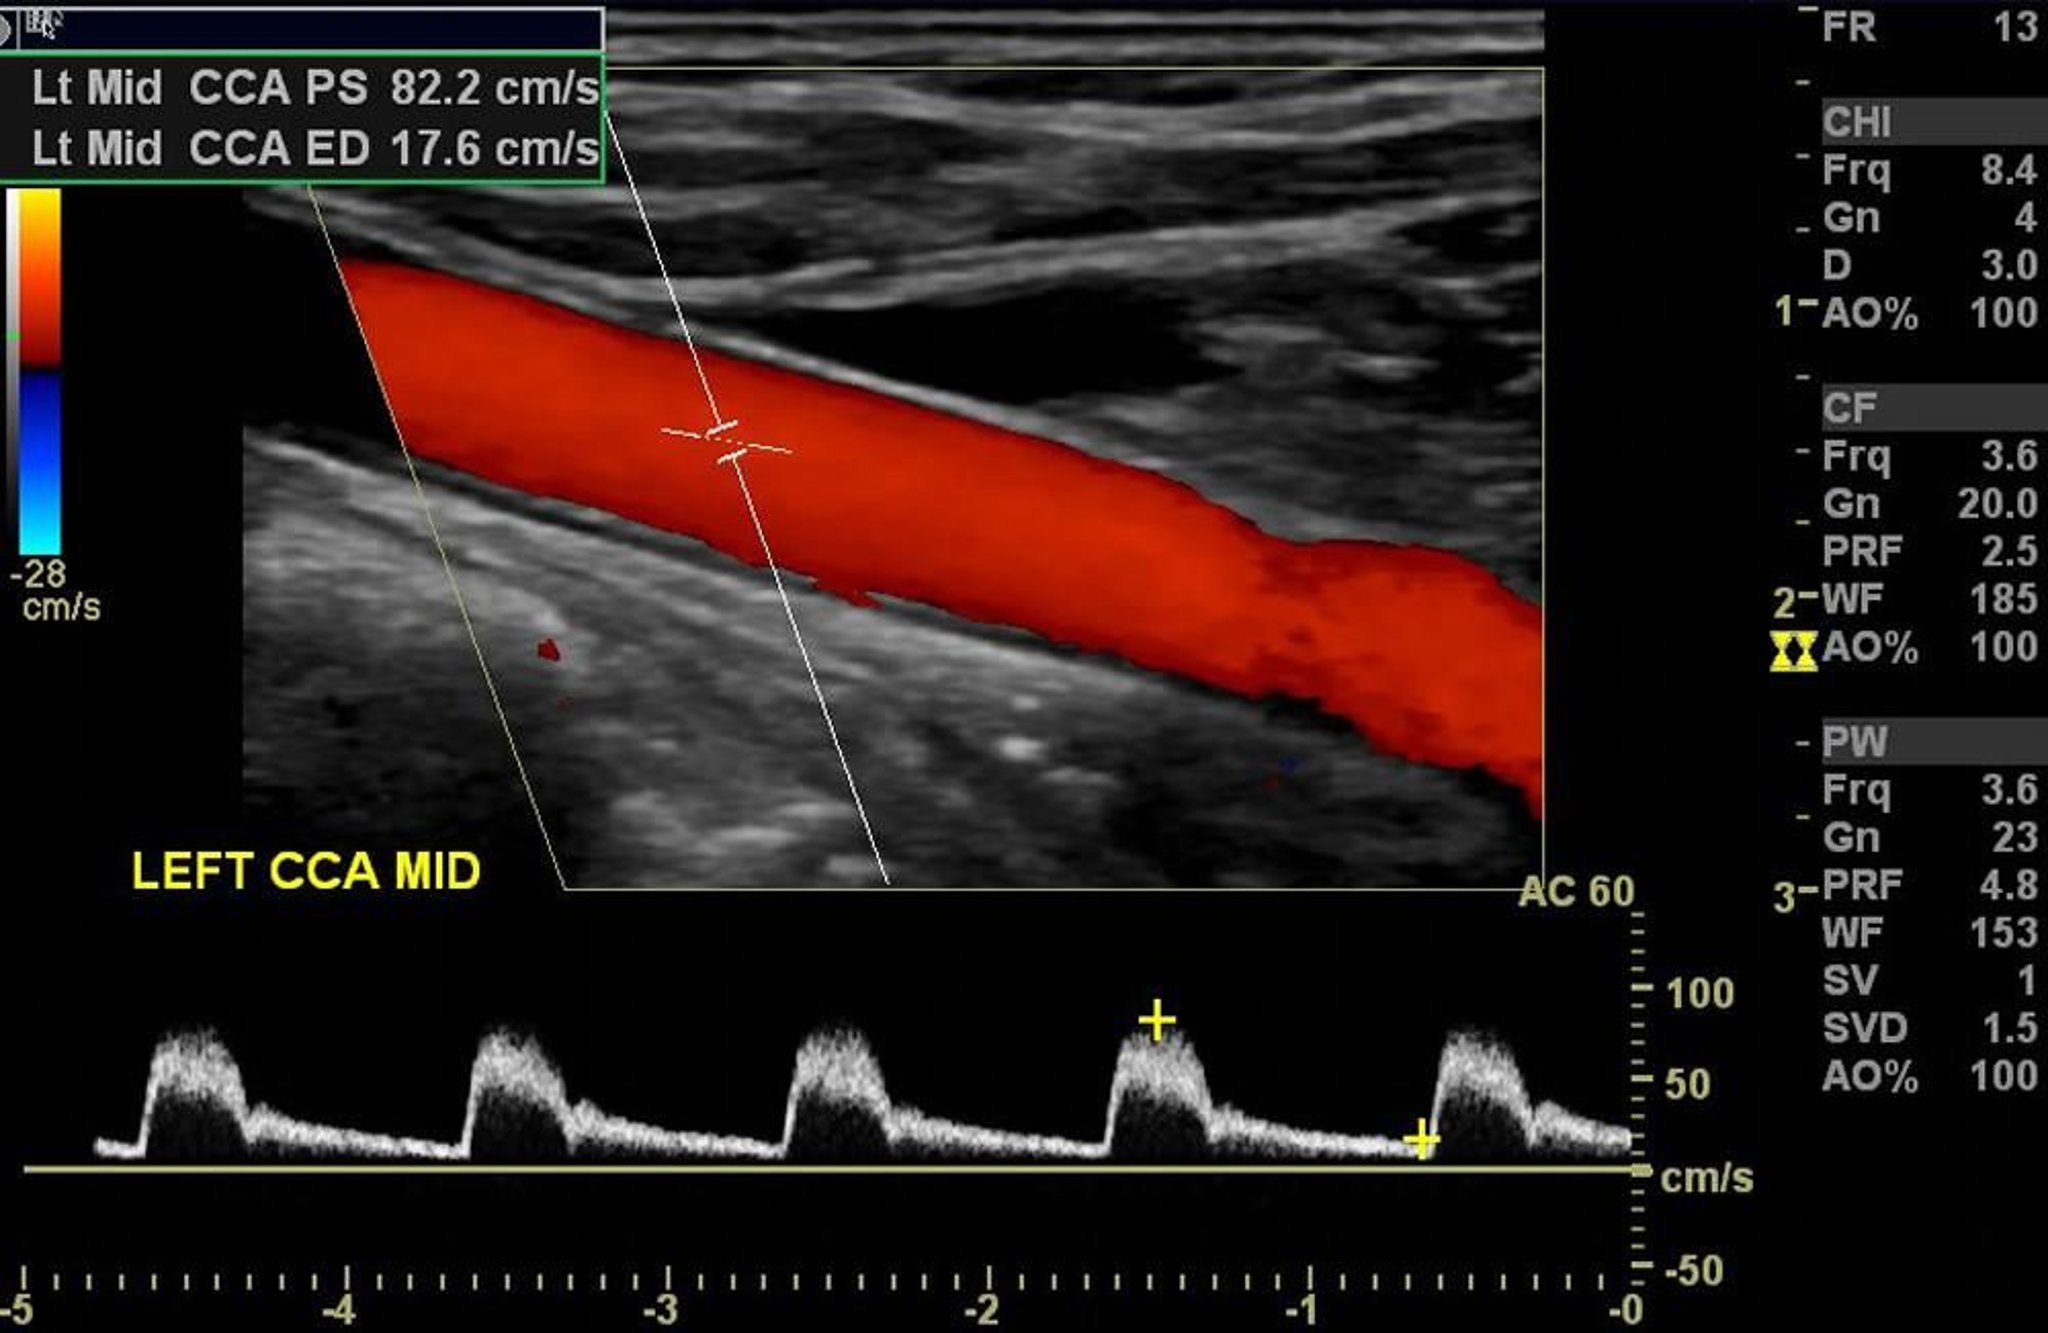

Ultrassonografia Doppler colorido da artéria carótida esquerda mostra fluxo arterial normal sem estenose significativa.

Imagem cedida por cortesia de Hakan Ilaslan, MD.